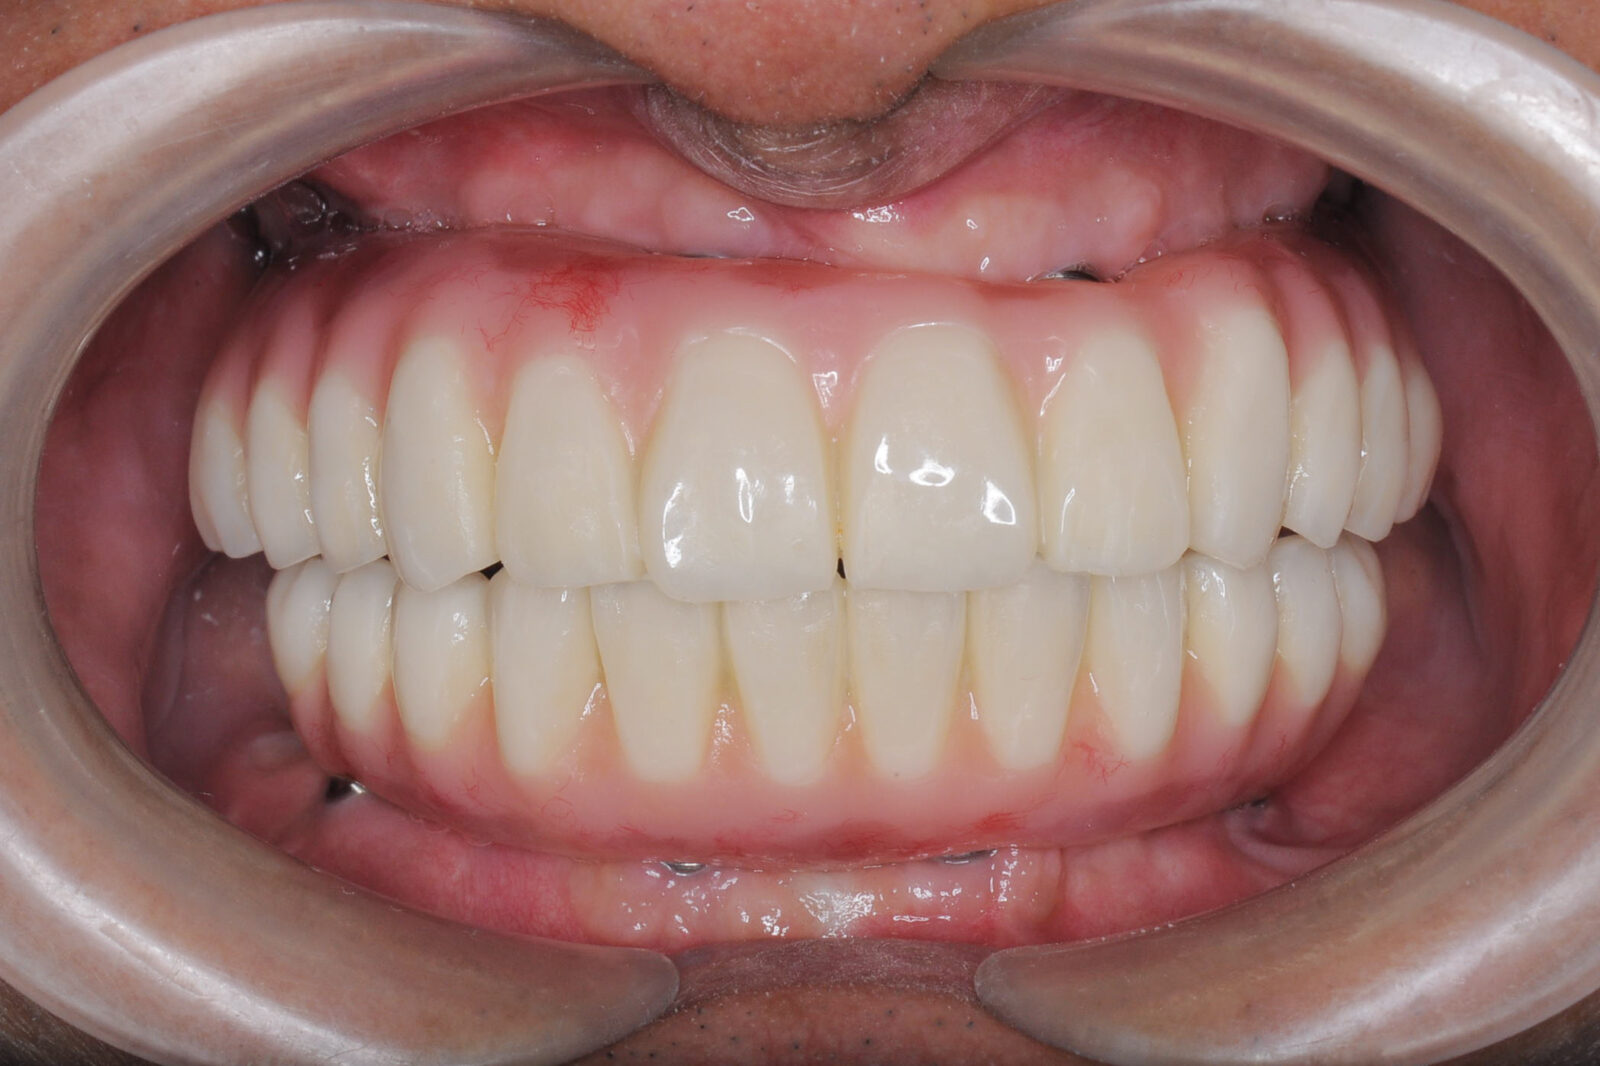

こちらの写真は、上下の顎をオールオン4で治療した際のビフォーアフターを示しています。

歯や歯茎が自然な色合いを持っていることにご注目ください。

オールオン4で変わる顔の印象

当院でオールオン4を装着すると、口元にハリが出て、余分なシワが和らぐことがあります。

その結果、顔全体が若々しく見えることがあります。

ただ単にオールオン4を入れれば良いというものではありません。

当院では、患者さん一人ひとりに合わせて慎重に噛み合わせや歯の形、配置を調整しています。

これにより、お顔立ちにも若々しい変化をもたらせます。

「しっかり食べられる喜び」と「若々しい顔立ち」の両方を手に入れ、より充実した毎日を楽しんでいただけるようサポートしています。